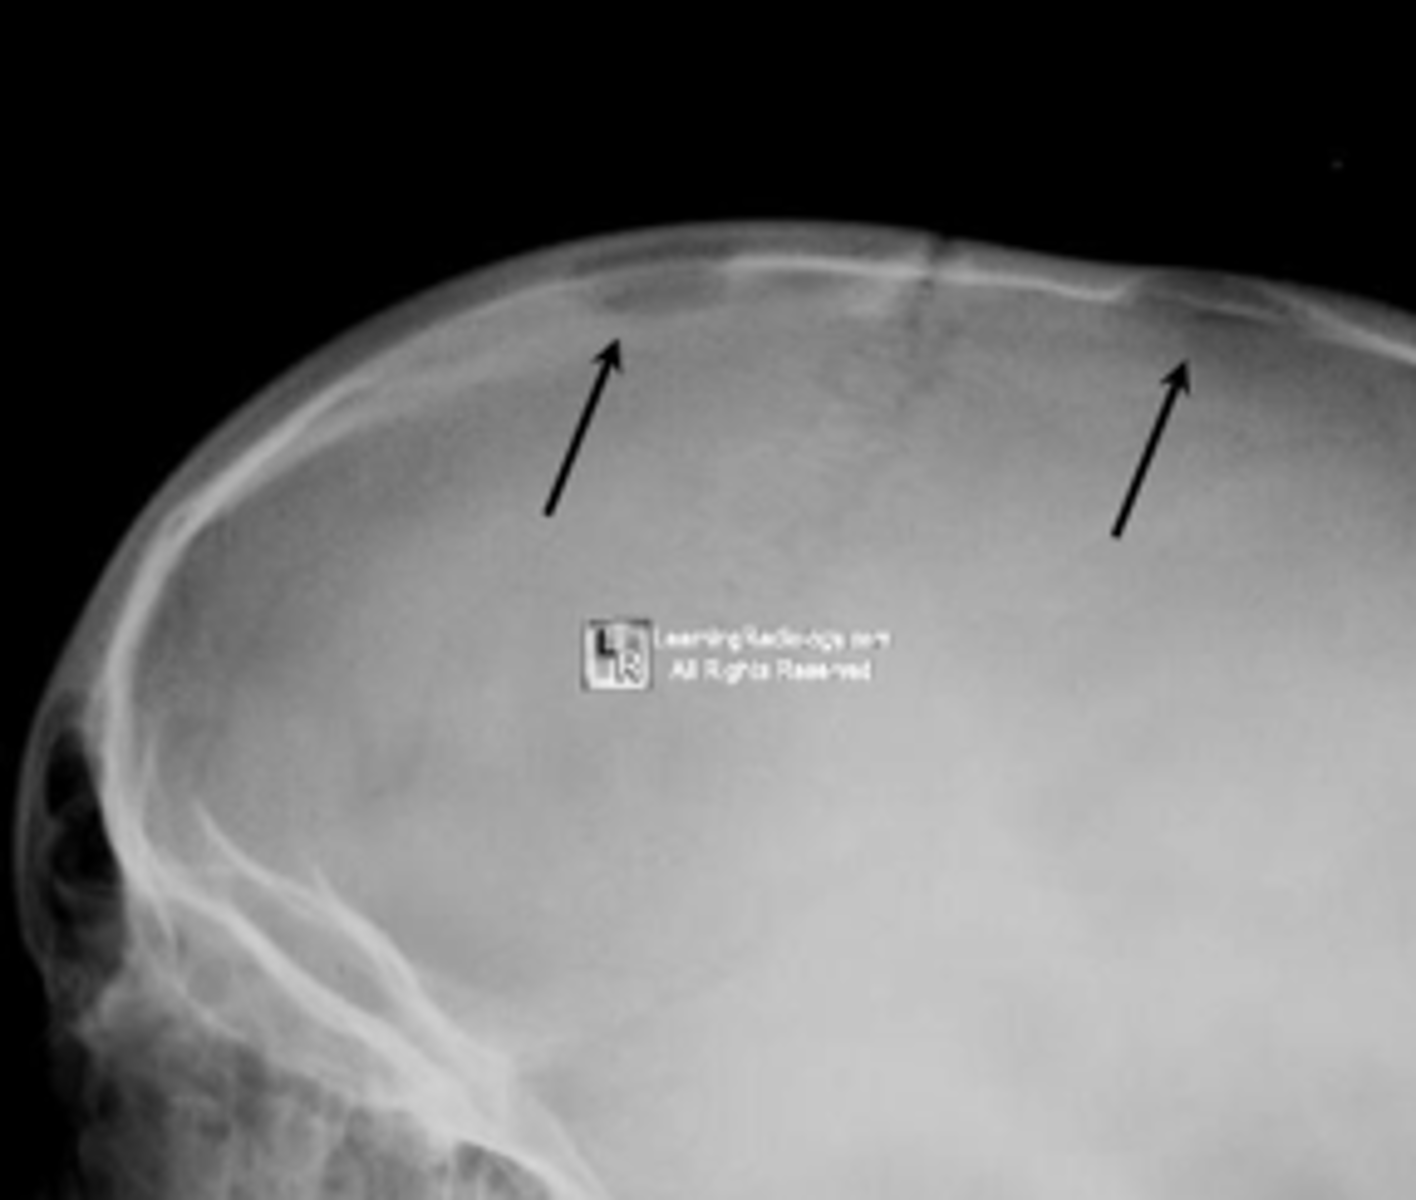

Eosinophilic granuloma

- <20 y.o. (peak 5-10 y.o.)

- Skull, mandible, pelvis, spine

Beveled edge

ID radiographic feature of eosinophilic granuloma in the skull

Button sequestrum

ID radiographic feature of eosinophilic granuloma in the skull